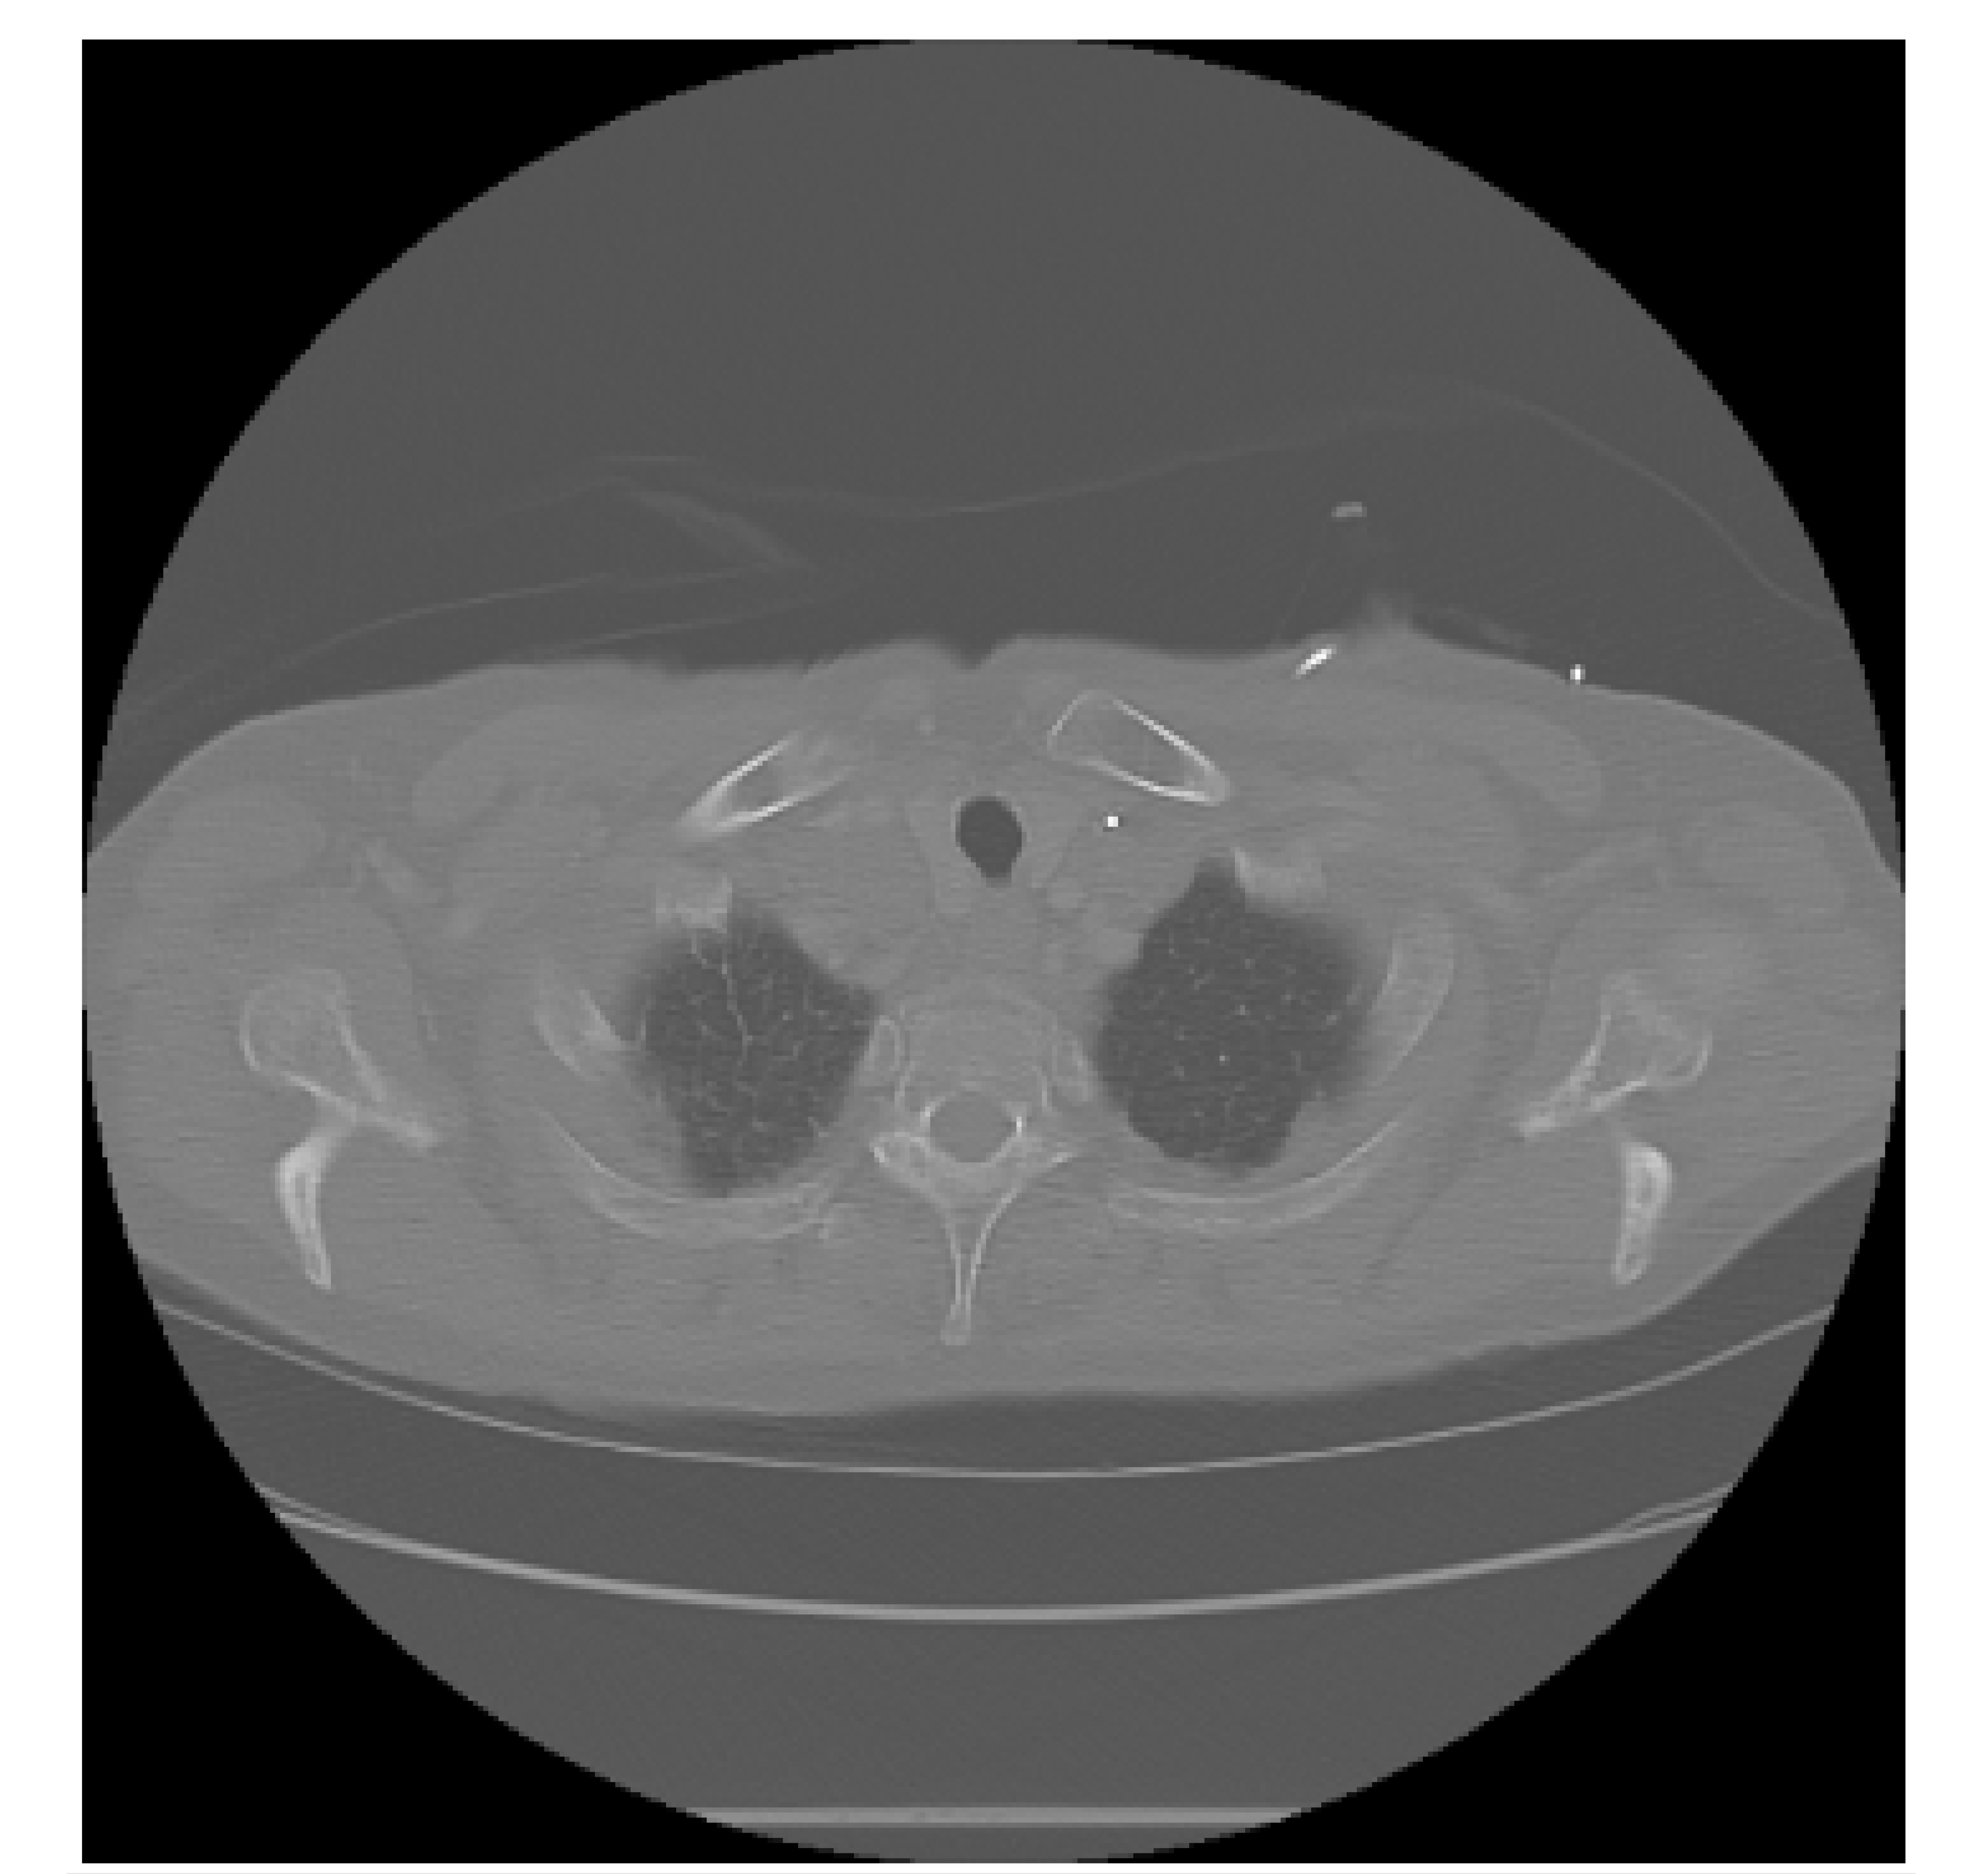

The APILungCancer interface provides intuitive functionality for loading and analyzing DICOM medical images. In the Load DICOM Images section, users can select and process CT scans for lung cancer evaluation. Once an image is loaded and analysis is performed, the software presents a visualization of the image along with the predicted probability of cancer (Table 7). Our study focused on lung cancer, including subtypes such as adenocarcinoma, squamous cell carcinoma, and small cell carcinoma. About 1000 training images and 300 test images from the CMB-LCA dataset were used to develop and validate the system.

In this example (Figure 5), the DICOM image 1-27.dcm from the test set was processed and the software calculated a cancer probability of 0.4267 (42.67%), indicating a high likelihood of malignancy.

Figure 5.

Determination of the probability of lung cancer. Example output of the system for the image 1-27.dcm, yielding a predicted probability of 42.67%, consistent with Table 7.

This value matches the result in Table 7, confirming the consistency of the predictions generated by the AI-based model integrated into the system.